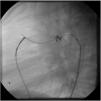

Both patients with history of previous PDA closure were successfully treated. The first was a seven year-old child who had a coil implanted at age three. The procedure was technically difficult, requiring a guidewire capture using a snare catheter to go through the residual PDA (Figure 11), and an Amplatzer duct occluder II 3x4 mm device was implanted successfully. The second patient was a 19 month-old child with PDA and pulmonary hypertension after an unsuccessful surgical ligation. In this case, sizing with a Tyshak balloon was required before implanting an Amplatzer duct occluder II 3x4 mm device (Figure 12).